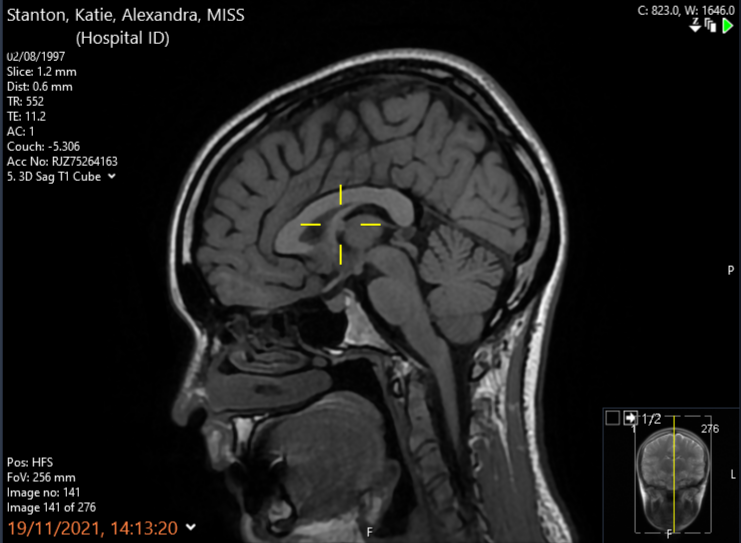

In August 2021 I received my diagnosis; an intraventricular tumour called a colloid cyst, located within the third ventricle of the brain – which is right in the middle. The cyst was found after a long string of headaches lead me to urgent care with visual disturbances, resulting in a referral for a CT scan. The scan revealed the cyst at an early stage, and thankfully no sign of hydrocephalus (cerebrospinal fluid building up around the brain due to the cyst blocking the flow) meaning that I was able to be put on Watch & Wait with yearly monitoring scans every November.